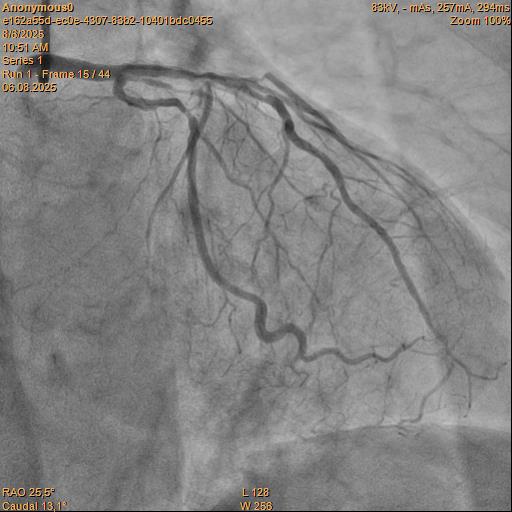

Angiography Right coronary artery dominance LEFT CORONARY ARTERY (LCA): trunk of the left coronary artery: uneven contours along the entire length. Left Anterior descending artery (LAD): uneven contours, stenosis in medial part by 80%. Circumflex artery (LCX): uneven contours along the entire length. RIGHT CORONARY ARTERY (RCA): uneven contours in the proximal segment, ¬³hronic total occlusion, the post-occlusionportion is fairly filled through intersystem collaterals.

The guide catheter was selectively placed at the RCA orifice, several attempts at antegrade recanalization were performed, after 10 minutes a decision was made to perform retrograde recanalization of the RCA, Sion Blue with the support of a Corsair 150cm microcatheter was successfully introduced through the septal branch into the middle segment of the RCA, escalation to Gaya 2 was performed and recanalization of the RCA was performed. Tip-In was performed in the antegrade guide catheter, the retrograde coronary guide was fixed with a balloon catheter. The retrograde microcatheter was advanced into the proximal segment, however, when performing Corsair, its defragmentation occurred, and the tip of the microcatheter itself was torn off. A decision was made to perform repeated recanalization of the RCA in a new lumen. Recanalization was successfully performed, then Tip-In was performed into the antegrade microcatheter and its successful passage beyond the occluded area. Balloon angioplasty and stenting of the RCA under OCT control with vFR.